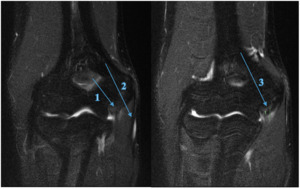

A 17-year-old amateur male Javelin thrower (State Representative) presented with right elbow pain which occurred during a competition 4 days prior. He described an audible pop and sharp pain experienced just before releasing the javelin. In the six weeks prior to the competition, the athlete experienced minor discomfort 3/10 (NRS) in the shoulder and medial elbow, which would ease at the completion of training and competition. As presented in Table 2 the physical examination findings, there was obvious swelling and palpatory tenderness over the medial elbow joint line (UCL/FCU & FDS tendons) and the medial epicondyle. The medial elbow dysfunction was exacerbated by any gripping or pronation motion reporting an 8/10 (NRS) at worst, reducing to 4/10 with the influence of ice, anti-inflammatories and analgesics as presented in Table 2 and 3. All activities ceased immediately until the pain and swelling was reduced. Due to the mechanism of injury and clinical findings, the practitioner referred him for MRI (Figure 3) which revealed a full thickness tear to the anterior bundle of the UCL with a low-grade partial tear of the FCU muscle, distal to the common flexor origin, which dictated the treatment choices and future modification to the training program.

Imaging

MRI has typically been the gold standard imaging modality in identifying tendon and ligament pathology such as UCL injuries, particularly when full-thickness tears are present.10,51,52 Athlete A’s UCL injury was diagnosed by physical examination and confirmed by MRI (Figure 2), and Athlete D (Figure 3) also had diagnoses confirmed by MRI.

The sports chiropractors decided not to refer Athlete B for imaging, rather using their clinical experience, the athlete’s history and clinical presentation to make a working diagnosis of pathological findings and initial conservative management. Athlete E was referred for x-ray (Figure 4) 5 days post injury incident to confirm a fracture to the medial epicondyle (Little Leaguers Elbow), after clinical examination suggested its likeliness.

The treatment and management was not dictated solely on these imaging findings, but in conjunction with the physical examination and clinic history.